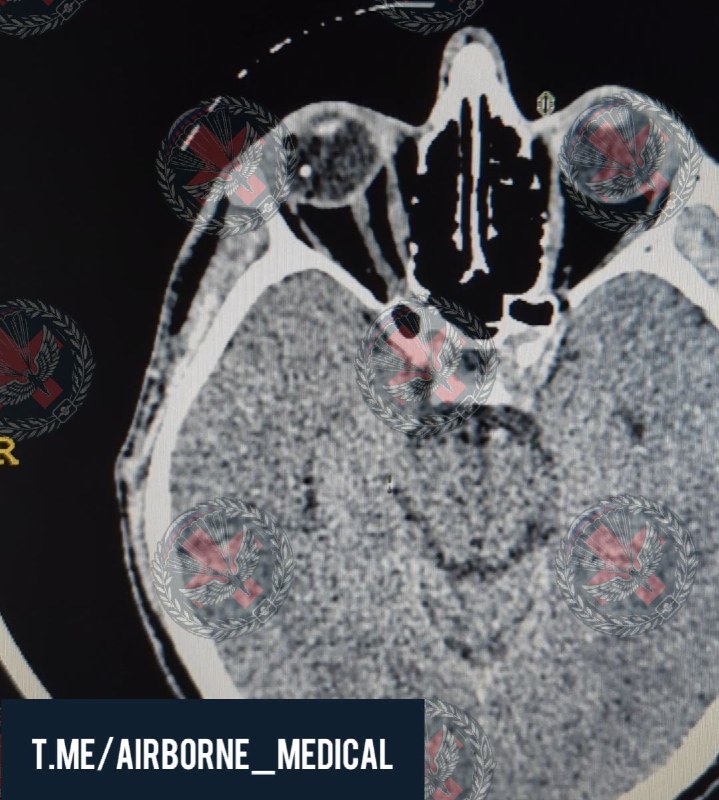

2024-08-10 12:32:41

Пациент после ДТП на передовой срочным образом был доставлен в госпиталь. Практически сразу же отправился в операционную

Диагноз: Тяжёлая закрытая черепно-мозговая травма, ушиб головного мозга средней степени тяжести со сдавлением острой субдуральной гематомой левых лобной, височной, теменной и затылочной долей, дислокационный синдром

Выполнено:

Первичная левосторонняя декомпрессивная гемикранэктомия

Удаление острой субдуральной гематомы

Расширенная пластика твердой мозговой оболочки свободным лоскутом надкостницы

Жизнь спасена, впереди длительный период лечения и реабилитации

Комментарии в видео